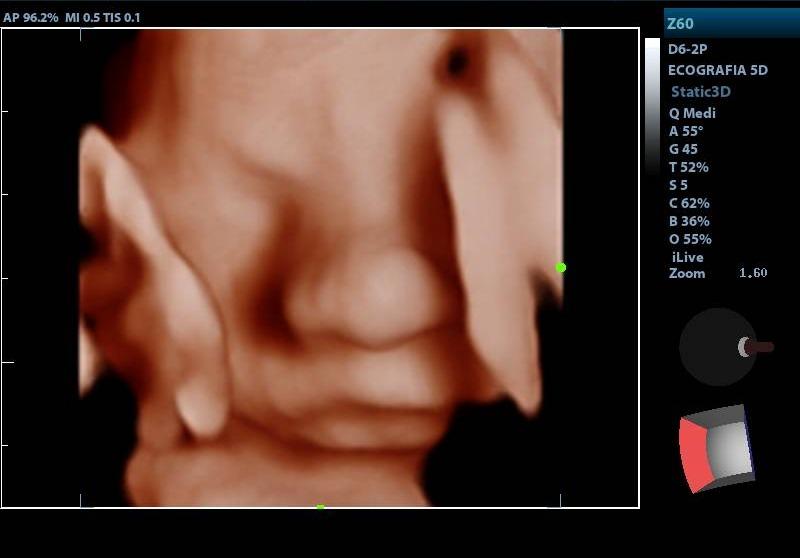

ECOGRAFIA OBSTETRICA 5D

SERVICIOECOGRAFIA

PRESENTACIÓNECOGRAFIA

CONDICIÓNCUALQUIER EDAD GESTACIONAL

TIEMPO20 MINUTOS

TIPO RESULTADOSIMAGENES ECOGRAFICAS

ESPECIFICACIONESIMAGEN TRIDIMENSIONAL EN TIEMPO REAL MEJOR NITIDEZ IMAGEN TRIMIDENCIONAL DEL FETO SE ESTUDIA BIOMETRIA FETAL ILA VALORACION PLACENTA LATIDOS CARDIACOS FETALES